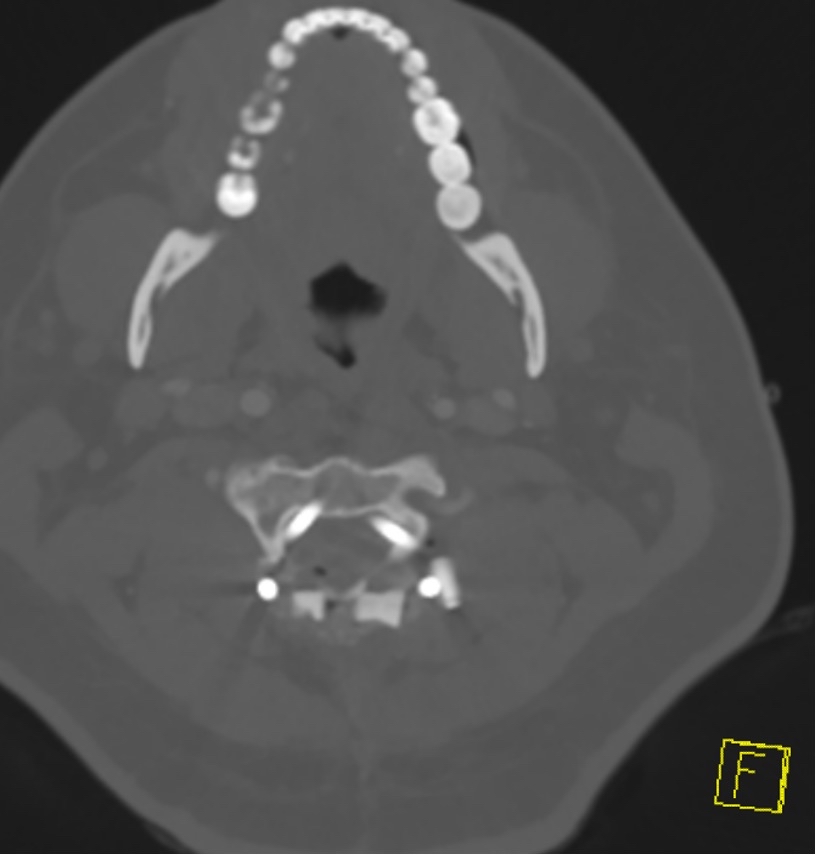

Xray

Frequently misses this injury

CT